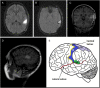

(A) Axial Fluid attenuated inversion recovery (FLAIR) magnetic resonance image demonstrating T2-based hyperintensity in the left parietal lobe, consistent with post-surgical resection cavity. (B) Axial susceptibility-weighted image (SWI) demonstrating susceptibility artifact surrounding the resection cavity, consistent with residual blood products. (C) Contrasted coronal T1 image showing heterogeneous contrast enhancement of the resection cavity. (D) Sagittal view of the FLAIR hyperintensity, lying immediately superior to the lateral sulcus and caudal to the primary somatosensory cortex. (E) Somatotopic map of the secondary somatosensory cortex (SII; green region) in relation to the primary somatosensory cortex (SI; blue region), with bordering central sulcus (yellow margin), lateral sulcus (red margin), and superior parietal cortex (SPC; purple region).